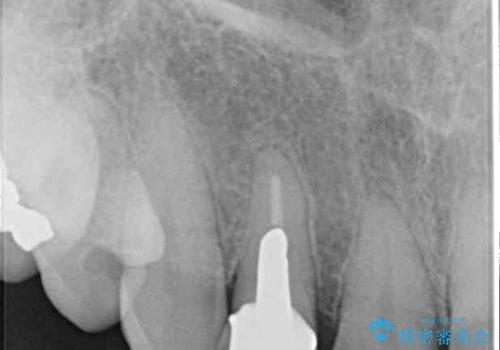

元々磨き残しによる歯肉の腫脹がありましたが、クラウンが歯肉深くに装着されていたため、特に腫脹が目立っていました。

仮歯に置き換えた際に歯周外科処置を行い、歯肉の腫脹が落ち着いたことを確認してオールセラミッククラウンにて補綴することとしました。